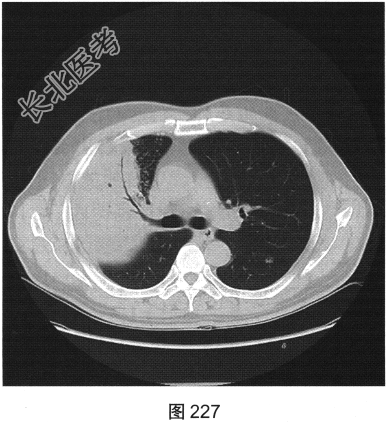

- [材料题] 患者男性,30岁。受凉后出现寒战、高热、咳嗽1天来医院就诊,听诊右上肺呼吸音减低。

- 简答题2、患者行胸部CT检查,如图227、图228所示。请问患者胸部CT可见哪些影像学表现?